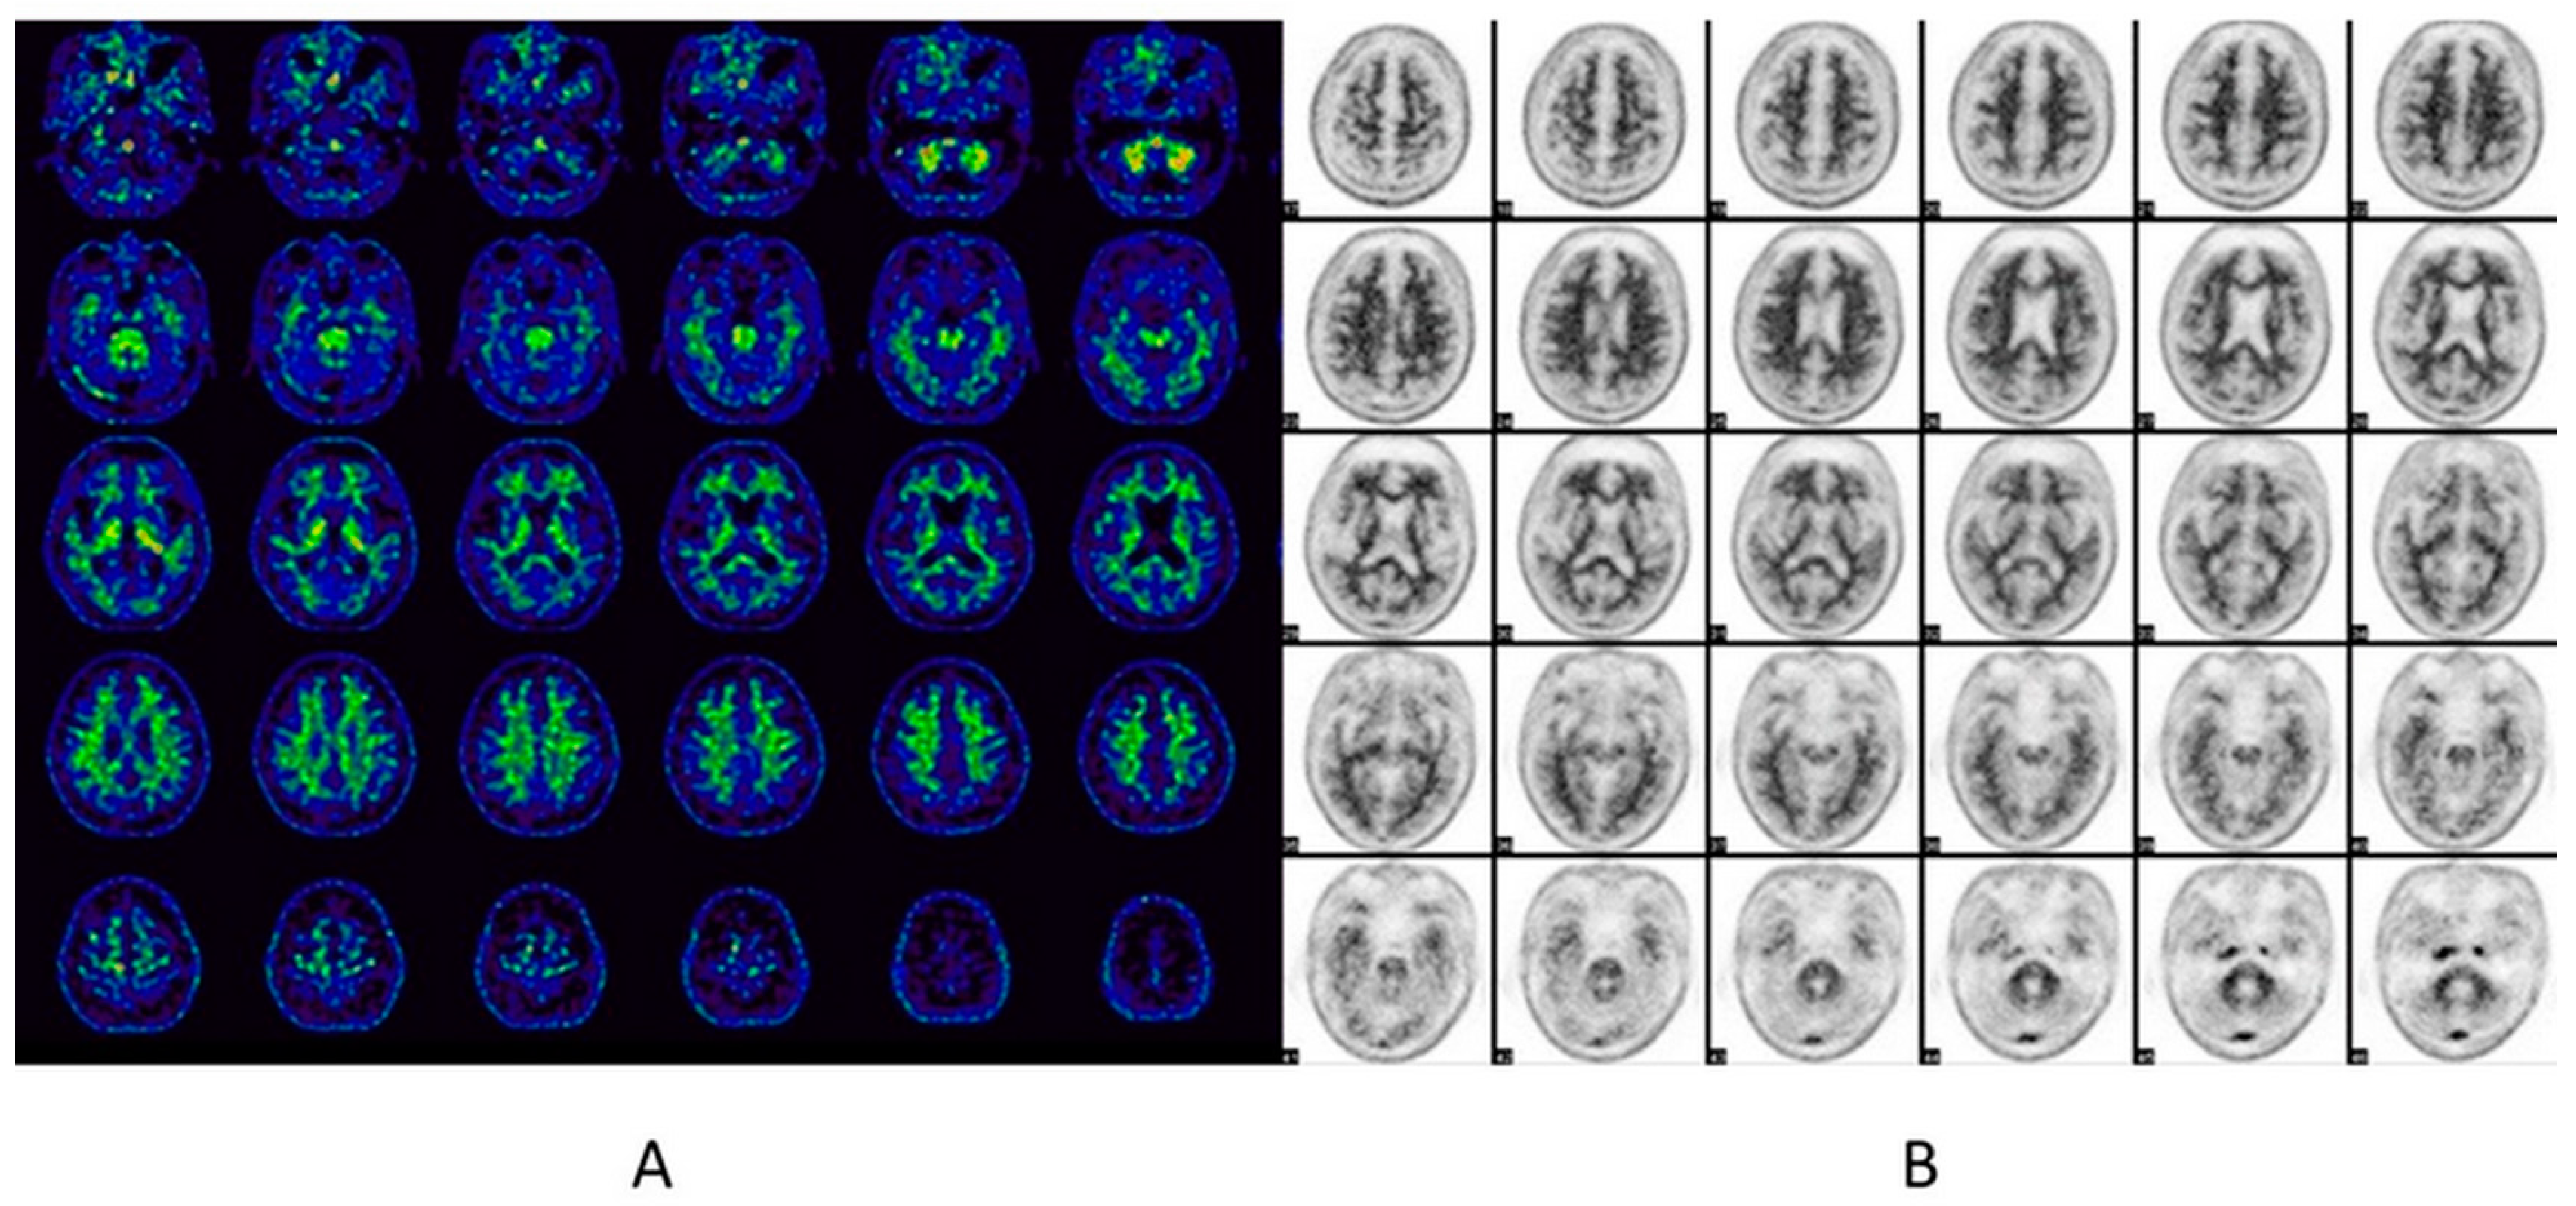

6.2. Brain Amyloid PET

6.2.1. Imaging Data Display [39]

- Gray scale: 18F-florbetaben

- Color (Rainbow): 11C-PiB, 18F-flutemetamol and 18F-NAV4694

- Reverse gray scale: 18F-florbetapir

- Maximum intensity of the display scale

- 18F-florbetapir: the brightest region of overall brain uptake

- 18F-florbetaben: the white matter maximum

- 18F-flutemetamol: setting the scale intensity in the pons region to 90%

6.2.2. Image Interpretation for Brain Amyloid PET

Visual Analysis [39,66,67,68]

Negative Scan

Positive Scan

| Radiopharmaceuticals | Color Scale | Criteria For Positive Scan | Cortical Region | SUVR Cut-Off for Positive Scan | Reference Region |

|---|---|---|---|---|---|

| 11C-PiB | Color (Rainbow) | Binding in GM > WM | N/A | 1.4–1.6 | Cerebellar cortex |

| 18F-florbetapir | Black/white (Reverse gray) | Loss of GM/WM contrast > 1 region | Temporal > occipital > prefrontal > parietal | 1.1–1.34 | Whole cerebellum |

| 18F-flutemetamol | Color (Rainbow) | Increased GM uptake or loss of GM/WM contrast > 4 cortical and 1 subcortical regions | Frontal > posterior cingulate/precuneus > insula > temporal > striatum | 0.58–0.62 | Pons |

| 18F-florbetaben | Black/white (Gray) | Increased GM uptake extending to the cortical margin > 4 cortical regions | Lateral temporal > frontal > posterior cingulate > parietal | 1.43 | Cerebellar cortex |

| 18F-NAV4694 | Color (Rainbow) | N/A * | N/A * | 1.4–1.5 | Cerebellar cortex |